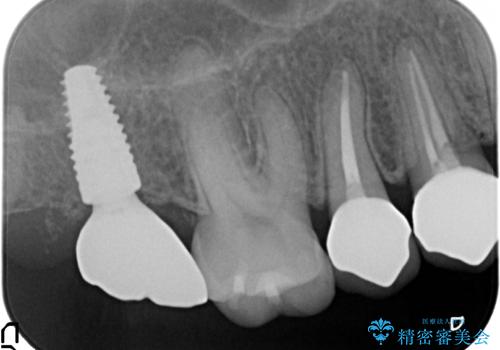

インプラントを用いた臼歯部欠損補綴

- 上下1本づつの歯を失い、噛めないことの改善を求めて来院されました。

保存可能な歯の虫歯・根管治療を行い、喪失した部分はインプラントを埋入、オールセラミックジルコニアクラウンを製作し審美的に仕上げていきます。

今回下顎の欠損部位はブリッジも検討されましたが、並行性の観点から最後方臼歯の神経を取るリスクを抑えるためインプラント治療を選択しました。